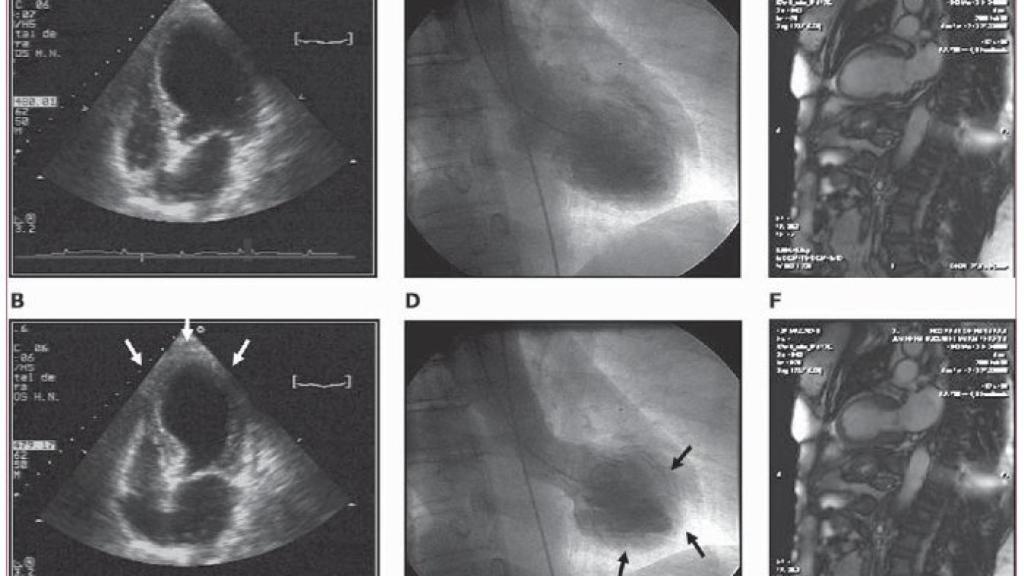

Un ecocardiograma en las primeras horas de una miocardiopatía de takotsubo.

Por otro lado, y para que no haya errores de concepto, recordemos que sí existe el síndrome del "corazón roto", muchas veces desencadenado por factores emocionales. La miocardiopatía de Takotsubo es una enfermedad cardíaca que se produce por la debilidad del músculo cardíaco tras un gran estrés emocional.

Esta enfermedad suele confundirse con un infarto de corazón, pero no lo es. No se produce ninguna rotura cardíaca ni lesión física como tal, sino una alteración de la contractibilidad del músculo cardíaco, que puede mejorarse con fármacos.